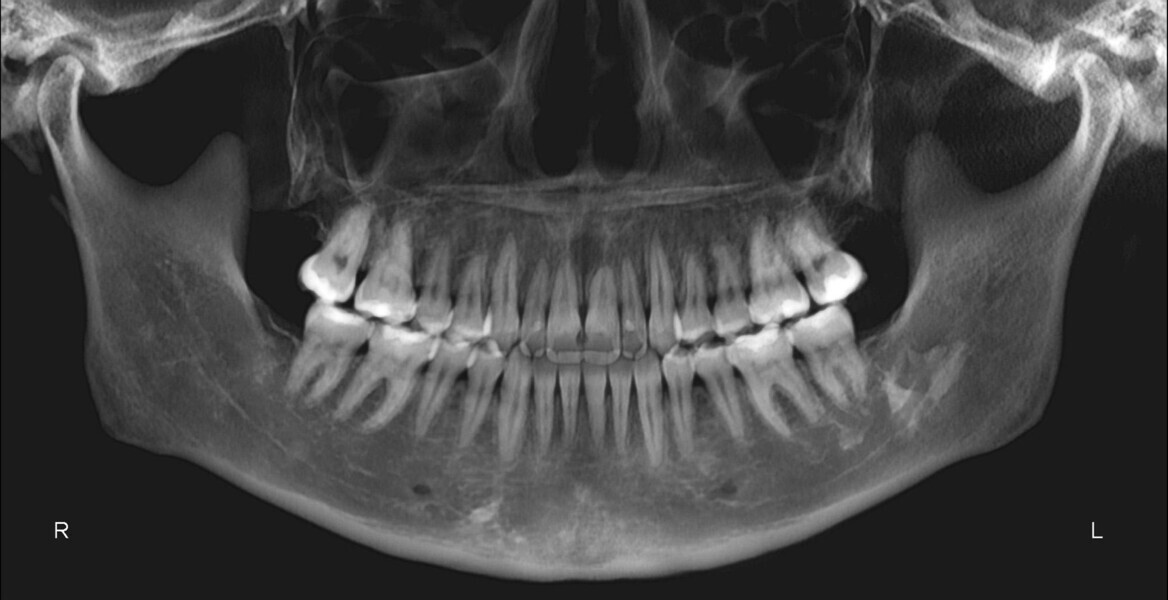

The panoramic radiograph confirmed the presence of all four third molar germs. Notably, there was advanced root resorption in the maxillary arch, although the overall periodontal health appeared good (Fig. 3). The cephalometric analysis showed a Class II skeletal pattern, a vertical growth tendency and posterior mandibular rotation. The maxillary and mandibular incisors were found to be slightly proclined (Fig. 4).

The panoramic radiograph showed prior extraction of all third molars, localised root resorption of several teeth, generally good periodontal health and an atypical condylar morphology, suggestive of temporomandibular joint (TMJ) remodelling or degenerative changes (Fig. 19). The cephalometric radiograph and tracing revealed a mesobrachyfacial skeletal pattern and a tendency towards a Class II skeletal pattern (Fig. 20).

The post-treatment panoramic radiograph showed good root parallelism and no worsening of the pre-existing root resorption or periodontal condition (Fig. 32). The final cephalometric radiograph and tracing showed that, although the patient retained a Class II skeletal pattern, the values had improved owing to mandibular auto-rotation (ANB from 6.9° after splint therapy to 4.4° at the end of treatment). This auto-rotation had also improved the vertical measurements between the end of splint therapy and the end of treatment: maxillary inclination (SN–OP) had decreased from 18.6° to 16.2°, Ricketts’ facial axis from 92.7° to 91.4° and Jarabak’s sum of angles from 392.0° to 387.6° (Fig. 33).

The final panoramic radiograph showed good root parallelism and confirmed that all treatment objectives had been met without root resorption or harm to periodontal health (Fig. 49). The final cephalometric radiograph and tracing confirmed the mandibular auto-rotation: a facial axis of 95° pretreatment to 97° post-treatment and an anterior facial height of 117.5 mm pretreatment to 115.9 mm post-treatment (Fig. 50).